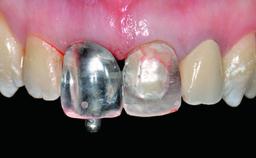

Replacement of a Missing Upper Left Central Incisor: Late Placement of an RC Bone Level Implant, CAD/CAM Zirconia Abutment

Eduardo R Lorenzana, Jason R Gillespie

A healthy 37-year-old female patient was referred for a consultation on the replacement of missing tooth 21 with an implant-supported restoration. She stated that several years previously the tooth had been traumatically avulsed following a motor vehicle accident. The tooth was replaced with a three-unit fixed partial denture (FPD) immediately afterwards. Over time, she became disillusioned with the FPD and looked for a different option, including orthodontic therapy. She presented still in her orthodontic appliances, with the pontic sectioned free from the FPD but attached to the archwire. Her orthodontist felt that orthodontic treatment had been successfully completed, but nevertheless referred her before removing the appliances in case adjustments were necessary.

Abutment Type CAD/CAM